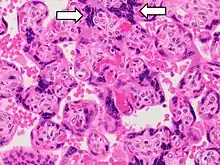

Histopathology of placenta with increased syncytial knotting of chorionic villi, with two knots pointed out.